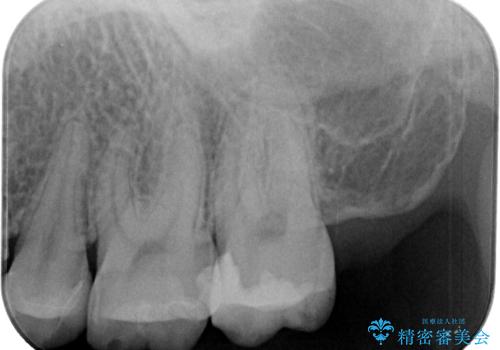

- プラスチックの詰め物が取れたとのことで来院された患者様です。神経の状態を検査し、正常な状態を確認してから残っている自分の歯の量を考慮しセラミックインレーにて修復しました。

拡大鏡視野下でコンポジットレジン、虫歯の除去を行い、セラミックインレーに適した形に整えました。

歯と歯茎の間に圧排糸と言われる糸を入れてシリコーン印象材にて精密な型どりをしました。

セラミックインレーの装着時には、唾液の侵入を防ぐために、ラバーダム防湿を行いました。